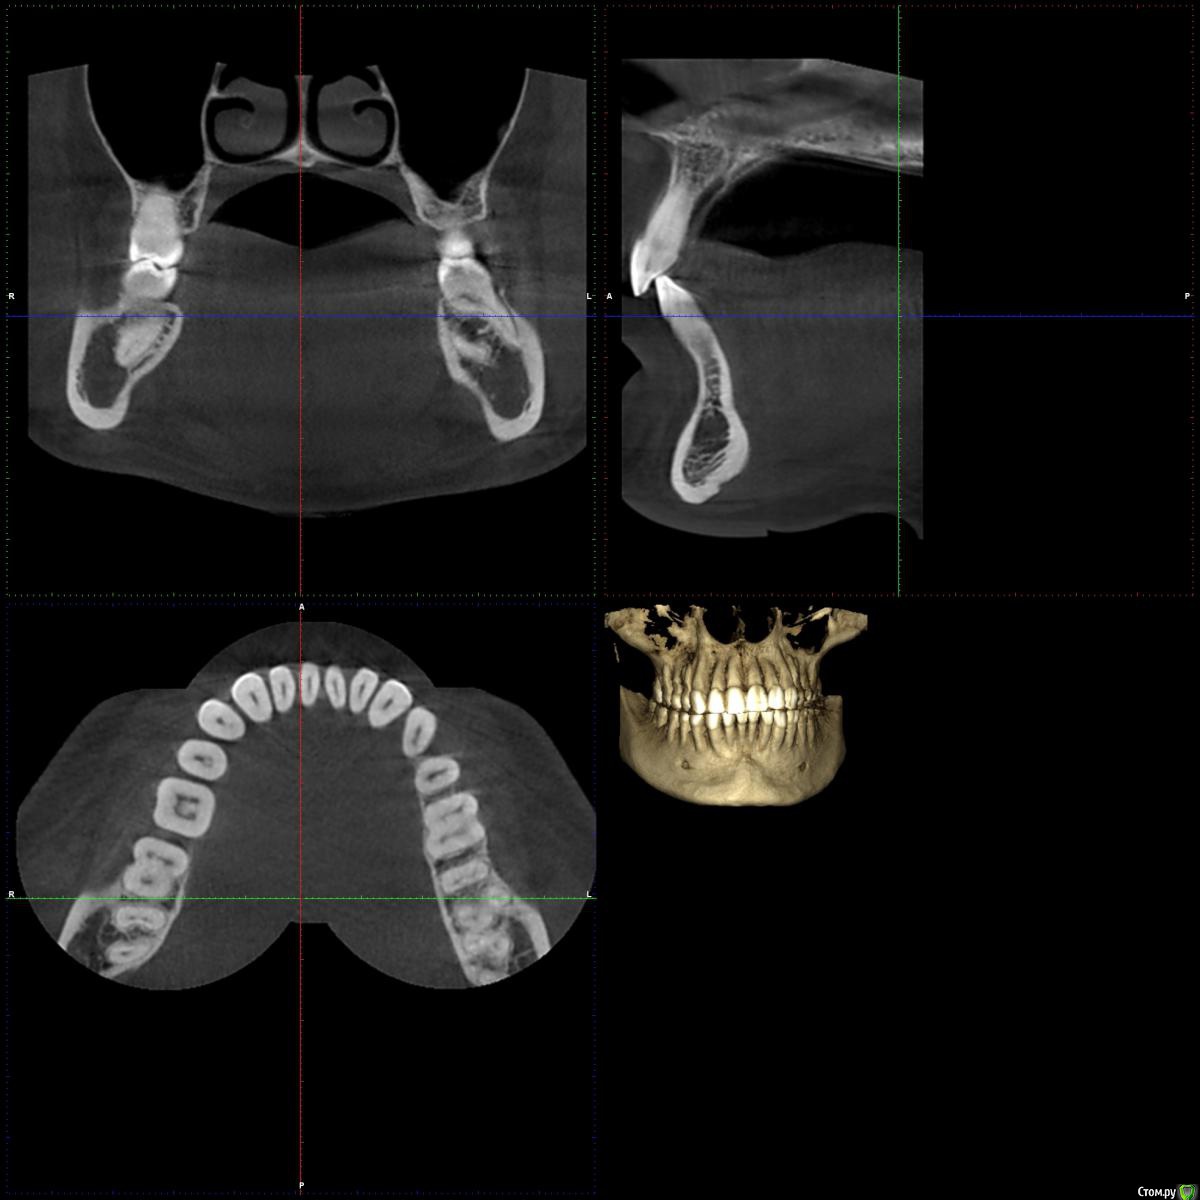

chuvashova_mv Опубликовано 18 июня, 2016 Поделиться Опубликовано 18 июня, 2016 (изменено) Мне 31 год. Тюмень. Сильное оголение корней каждого зуба. Сосочки на месте. Карманов нет. Тонкий биотип десны. Была у неск.ортодонтов, дело не в прикусе.Эндокринолог значит.отклонений не видит (щитовидка в норме, сах.диабета нет, менстр.регулярная сейчас, раньше были сбои), только имт 16,5. Есть ребёнок 3 года, заберем. сама.Гастроэнтеролог - хр.гастродуоденит со школы, желудок работает не в полную меру.Неврология - всд по гипотония.типу., бруксизма нет.Очень сух.кожа с рождения, особенно тяжко зимой.Прилагаются кт и оптг.Вопрос: все очень плохо? У нас в городе вызвались только два врача оперировать, но таких случаев как у меня у них не было.Нужна помощь пародонтологов-хирургов, кто с таким сталкивался. Изменено 18 июня, 2016 пользователем chuvashova_mv Ссылка на комментарий

faity Опубликовано 20 июня, 2016 Поделиться Опубликовано 20 июня, 2016 Судя по ОПТГ дисфункция и деформация ВНЧС, гипертрофия жевательной мускулатуры слева.По фото множественные рецессии и патологическая стираемость зубов.У вас классическая окклюзионная травма которая дала рецессию, стираемость, щелчки в суставе(если уже появились). Вам гнатолог нужен для начала ибо у вас причину сложнее устранить чем последствия в виде стираемости и рецессий.Зубы сжимаете во сне или во время бодроствования? 2 Ссылка на комментарий